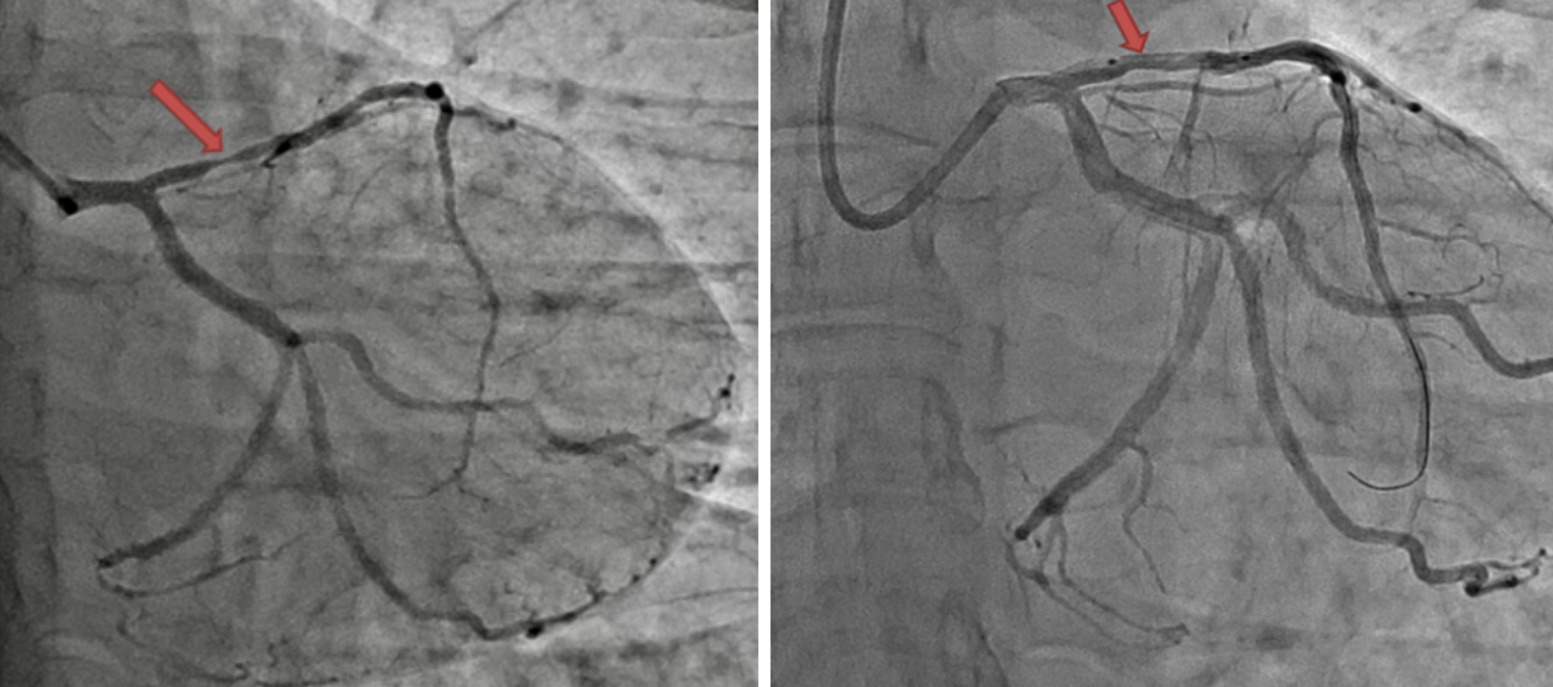

Заключение КАГ: ствол левой коронарной артерии не изменен, правая межжелудочковая артерия стенозирована в проксимальном сегменте на 85 %, далее неровности контуров, огибающая артерия – неровности контуров на всем протяжении, ветвь тупого края не изменена, задняя межжелудочковая артерия – не изменена, правая коронарная артерия – неровности контуров. Тип кровоснабжения – левый (рис. 2, а).

Рис. 2. Коронароангиографическое исследование (а), коронарная ангиопластика (б) пациентки Д. Фрагмент стеноза правой межжелудочковой артерии в проксимальном сегменте до вмешательства. Стент в расправленном состоянии в коронарной артерии. Результат после стентирования удовлетворительный

В связи с выявленным значимым стенозом правой межжелудочковой артерии было принято коллегиальное решение выполнить чрескожное коронарное вмешательство (ЧКВ) для оценки вероятности развития инфаркта – связанной артерии ПМЖВ.

На вторые сутки в отделении рентгенхирургических методов диагностики и лечения пациентке проведена баллонная ангиопластика с последующим стентированием коронарной артерии. Через интродьюсер введено 5000 ЕД гепарина, баллонная ангиопластика выполнена баллонным катетером 2,5´15 мм инфляцией 15 атм. На контрольной ангиографии остаточный стеноз 70 %. В область остаточного стеноза, в проксимальный сегмент правой межжелудочковой ветви позиционирован и имплантирован стент Biomatrix Flex 3,0´18 мм инфляцией 14 атм. Снимок в контроле: стент полностью расправлен, остаточных стенозов, диссекций и окклюзий боковых ветвей нет. Кровоток TIMI 3 (рис. 2, б).